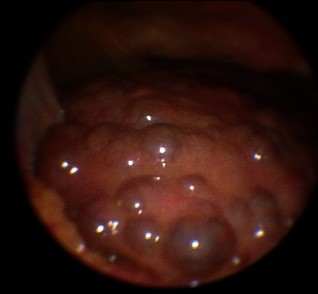

Leberzirrhose bei autoimmuner Hepatitis